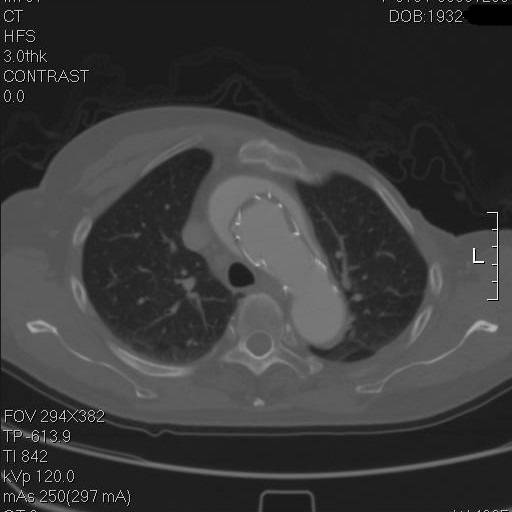

矢状面重建,胸骨钢丝很明显,方框示左颈总动脉,支架前端在假腔,后端在真腔。圆框示闭塞的人工血管

方框示左左锁骨下动脉,重度狭窄